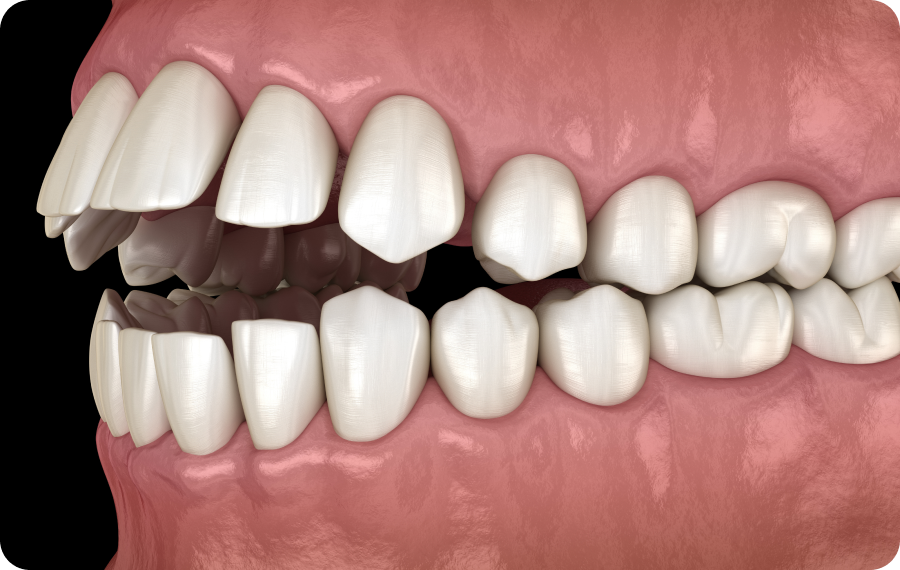

L’inversé dentaire et la déviation de la mâchoire inférieure correspondent à des désalignements entre les dents et les bases osseuses de la mâchoire. Dans une situation dite « idéale », les dents supérieures recouvrent légèrement les dents inférieures lorsque l’on ferme la bouche, et les arcades dentaires sont alignées. En cas d’inversé dentaire, ce rapport est perturbé : certaines dents inférieures viennent mordre devant les dents supérieures.

Cette anomalie peut être localisée (concernant seulement un petit groupe de dents) ou généralisée (affectant une grande partie de l’arcade).

Elle s’accompagne parfois d’une déviation de la mâchoire inférieure, c’est-à-dire un déplacement latéral ou antérieur du bloc mandibulaire par rapport à l’axe facial.